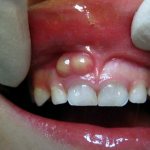

По мере развития гнойного процесса состояние ребенка становится тяжелее. Боли приобретают интенсивный пульсирующий характер. На десне формируется гнойный очаг виде небольшого образования белесоватого цвета на красном отекшем фоне. Вследствие активного воспаления развивается значительный отек мягких тканей лица. Если флюс появляется на верхней челюсти, то такой отек может располагаться не только на щеке, но и распространяется на околоушную область и глаз. Если локализация флюса на нижней челюсти, то отечность тканей может затрагивать и шейную область.

На фото: лечение флюса у ребенка в кабинете стоматолога